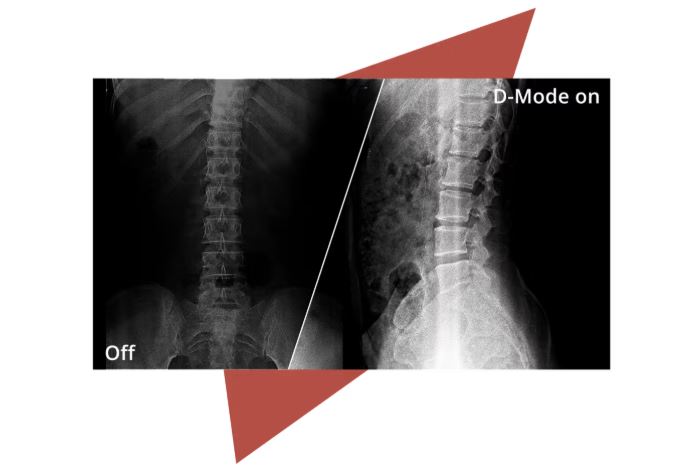

D-Mode

Profesionální monitor s přesností odstínů šedi pro rentgenové snímky.Režim D simuluje standard DICOM Část 14 a poskytuje stabilní a konzistentní výkon v odstínech šedi. Díky tomu lze lékařské snímky, jako jsou rentgeny, zobrazit s vyšší jasností a spolehlivostí v nediagnostických prostředích, jako je školení, konzultace nebo nemocniční administrativa.